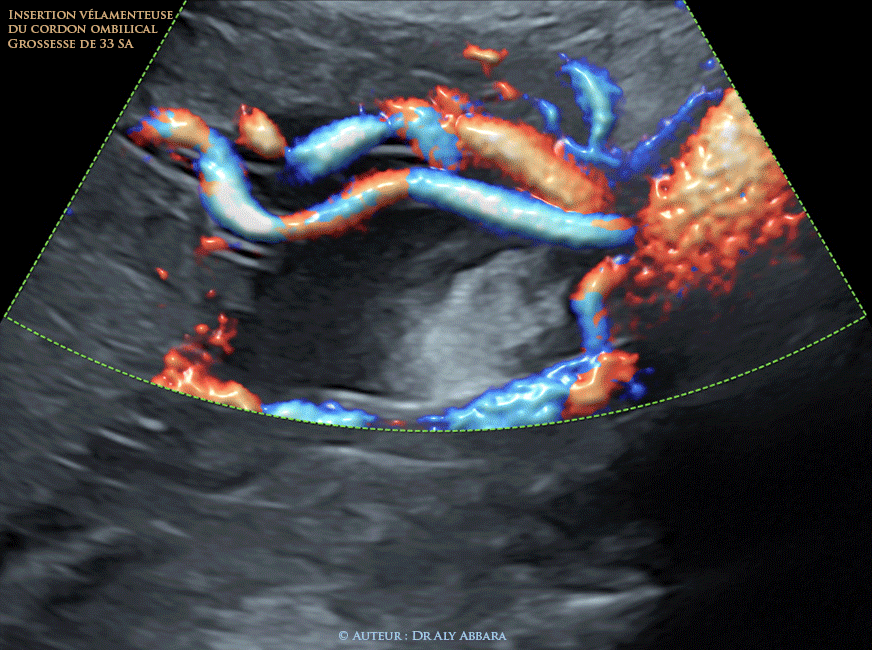

• Grossesse de 33 SA

• L'insertion vélamenteuse (ou en parapluie) ("1", "2", vue globale, vue partielle ; Echographie : insertion vélamenteuse du cordon ombilical vue échographique) :

• Vidéo échographique montrant une insertion vélamentesue du condon ombilical